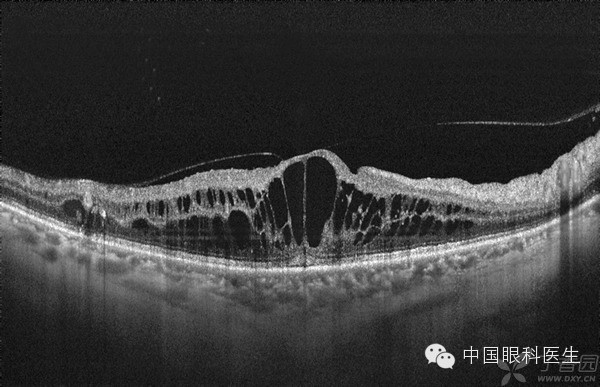

1.常规分类法:非PDR和PDR两型,其中PDR包含新生血管形成。新生血管比较脆弱,会出现不同程度的渗漏,如果任其发展,会出现纤维增殖现象,从而潜在引起玻璃体牵拉、玻璃体积血、牵拉性网脱等

当糖网影响到黄斑区时会出现糖尿病黄斑病变的称呼:

1.水肿是否影响到黄斑中心凹分为--中心或非中心的

2.水肿扩散区域的大小状态---局限性或者弥散性

3.黄斑周边的毛细血管状态---缺血性或者非缺血性

4. 混合型--以上各种现象均存在